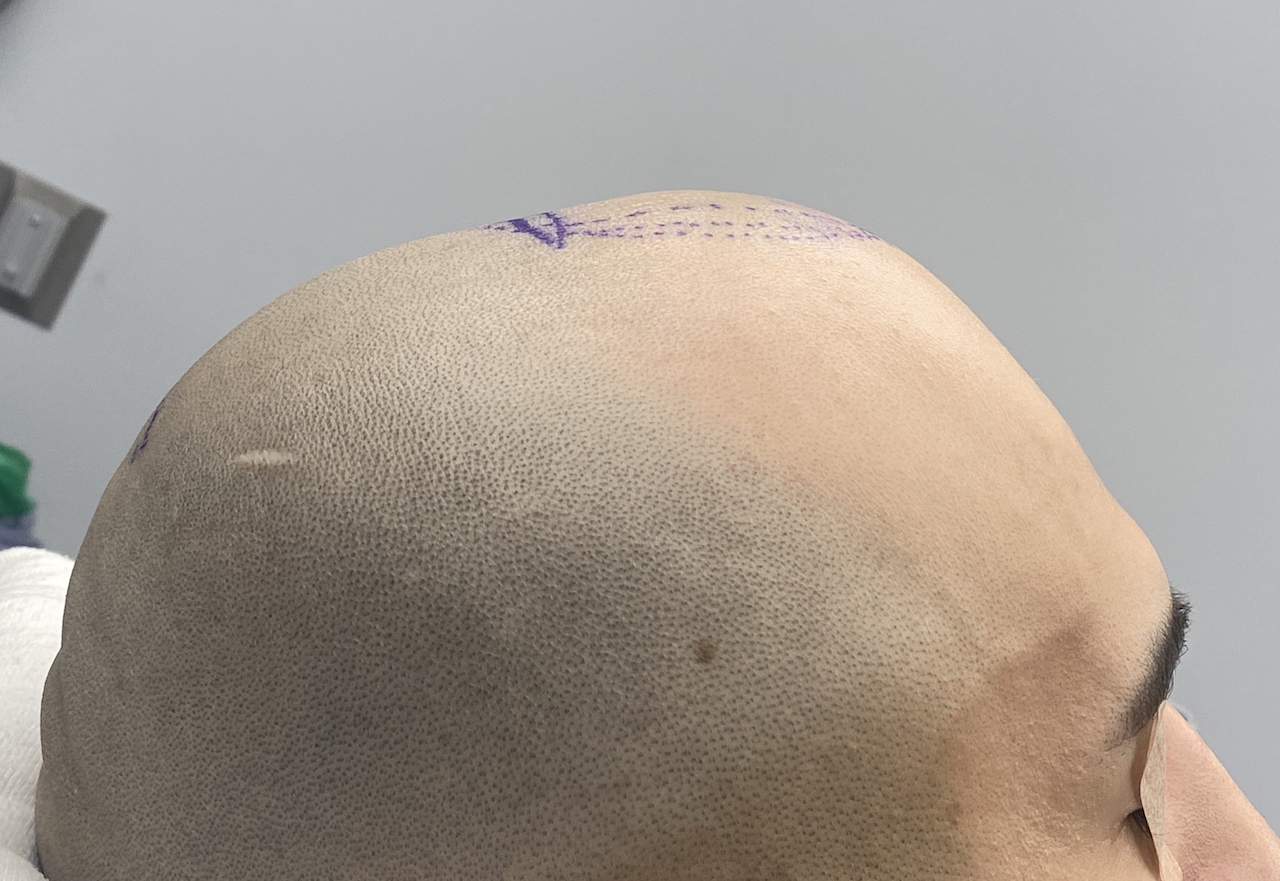

Desire for change of head shape from front view form an inverted V shape to a rounder and wider head shape.

Placement of custom extended forehead-temporal implants through incisions in the crease behind the ear. (he had a prior back of head skull implant which is green in the implant designs and which the head widening implants partially covered it)

Desire for change of head shape from front view form an inverted V shape to a rounder and wider head shape.

Placement of custom extended forehead-temporal implants through incisions in the crease behind the ear. (he had a prior back of head skull implant which is green in the implant designs and which the head widening implants partially covered it)